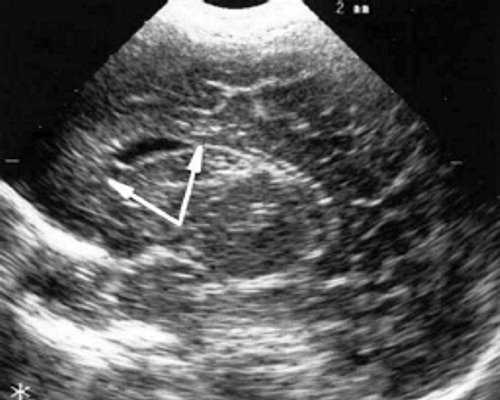

У детей этой группы при первом эхоэнцефалографическом исследовании были выявлены субэпендимально расположенные кистозные структуры на уровне таламо-каудальной вырезки (ТКВ) и (или) кпереди от нее диаметром от 0,3 до 1,1 см. У части новорожденных субэпендимальные кисты были представлены единой полостью с однородным или неоднородным содержимым, у других детей эти структуры напоминали соты, т. е. состояли из множества жидкостных включений, окруженных эхопозитивным ободком (рис. 3). Эти структурные особенности субэпендимальных кист, по-видимому, обусловлены разными стадиями резорбции. У 10 детей субэпендимальные кисты располагались в симметричных участках обоих полушарий, у 2 новорожденных - только в левом полушарии. У 3 детей, помимо субэпендимальных кист, расположенных в таламо-каудальной вырезке и (или) кпереди от нее, дополнительно выявлены субэпендимальные щелевидные кистозные структуры на уровне средних или передних отделов лобных рогов (см. рис. 3).

Рис. 3. Эхоэнцефалограмма ребенка Б. со смешанной герпес-цитомегаловирусной инфекцией, 5-е сут. жизни.

в) Правое полушарие. Стрелками обозначены субэпендимальные щелевидные кистозные структуры на уровне передних и средних отделов лобных рогов боковых желудочков.

г) Левое полушарие. Стрелками обозначены субэпендимальные щелевидные кистозные структуры на уровне передних и средних отделов лобных рогов боковых желудочков.